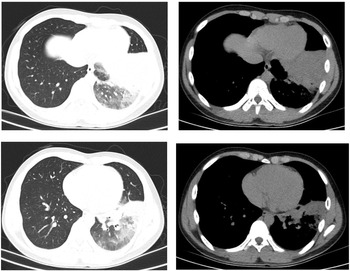

The patient was a 16-year-old male. He started to have fever 6 days prior to visiting our clinic. His maximum temperature was 40 °C. He had no respiratory symptoms and no abdominal pain. He exhibited morning diarrhoea with loose stools, accompanied by nausea and vomiting of small amounts of stomach contents. The patient visited our emergency department. The lung CT scans revealed ‘left lower lobe inflammation’. Results of a routine blood test were: leukocyte count 7.0 × 109/l, neutrophil count percentage 73.2%, neutrophil count 5.1 × 109/l, lymphocyte count 1.3 × 109/l, CRP 23.30 mg/l. The patient's condition did not improve after treatment with ceftazidime and intravenous infusion of azithromycin for 3 days. The patient experienced coughing with a small amount of yellow phlegm 2 days ago. The follow-up lung CT scans (Fig. 3) revealed ‘exacerbated left lower lobe inflammation, with areas of consolidation. The pleura was thickened at the left oblique fissure compared with previous scans’. The patient was admitted to the ward for further treatment.

Fig. 3. Chest CT of case 3.

Physical examination on admission: T: 40 °C, P: 99 beats/min, R: 20 breaths/min, BP: 110/71 mmHg. Harsh breathing sounds were detected in both lungs. No dry or moist rales were heard. Physical examination of the heart and abdomen showed no conspicuous abnormalities. The results of a blood gas analysis without oxygen therapy were as follows: pH 7.50, pCO2 29.5 mmHg, pO2 66.1 mmHg, HCO3 22.8 mmol/l, SO2c 94.7%. Pathogen testing on pharyngeal swabs obtained from the patient was positive for adenovirus DNA and negative for respiratory syncytial virus RNA, influenza A and B nucleic acids, mycoplasma pneumoniae DNA and novel coronavirus nucleic acids. The following tests were also negative: combined antigen/antibody test for HIV, mycoplasma IgM, and blood or sputum bacterial culture. The patient was administered the antiviral arbidol and a combination of antibiotics ertapenem and azithromycin. He recovered and was discharged after 12 days.